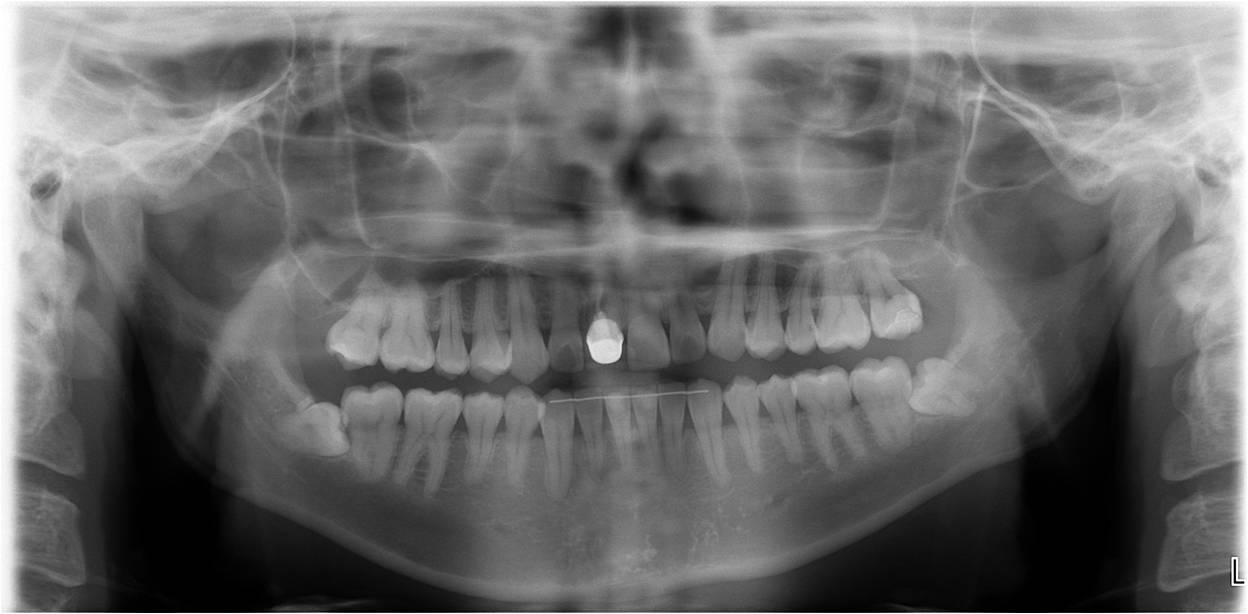

治療前,環口X光檢查,#38牙齒位不正